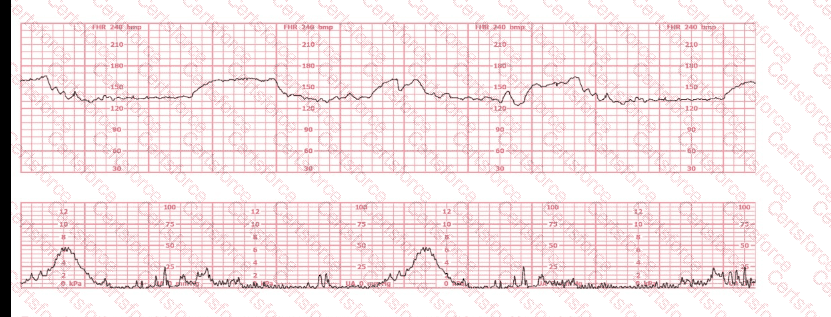

The tracing shown is a:

Question # 21

A.

Category I

B.

Category II

C.

Category III